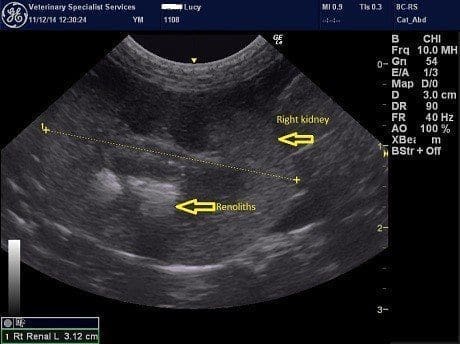

Following sedation, an abdominal ultrasound was performed focussed on the urinary tract. Both kidneys contained echogenic regions with distal shadowing consistent with renoliths (Figure 1). There was no evidence of hydronephrosis or hydroureter but both kidneys did show decreased cortical blood flow and increased cortical echogenicity. The urinary bladder revealed a focal change cranially which may reflect a scar from the site of the previous cystotomy. There was no evidence of bladder stones.

Figure 1. Ultrasound images of the left kidney (left) and right kidney (right). In both kidneys there is mineralised material (yellow arrows) with distal acoustic shadowing (white arrow).